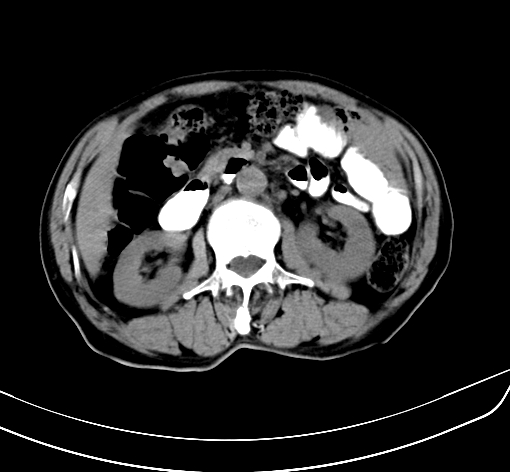

病人 男 70 咳嗽 胃部不适 2月余

胆囊壁增厚,与临近肝实质边界不清,临近肝实质内可见大片边界不清之低密度区,肝门区密度亦有减低,部分结构不清,尾叶前方可见块状影,肝右叶可见多枚边界不清之圆形低密度区,肝内胆管扩张征象,结合病史考虑1胆囊癌肝内转移,肝门区淋巴结转移,门脉癌栓待排2肝内胆管扩张3建议增强扫描

考虑胃癌肝转移,胆囊炎

肝脏多发大小不等低密度灶,边界不清,肝门区结构不清,肝内胆管轻度扩张,胆囊密度不均匀,内见软组织样密度影,与相临肝脏边界不清.考虑:1、胆囊ca侵犯肝脏并肝内多发转移,肺上也有结节影,转移?建议强化扫描.2、胃充盈不好,如怀疑有病变最好建议做相关检查.

胆囊壁增厚,周围模糊不清,肝内多发低密度影,胃充盈欠佳,胃壁增厚,外形尚规整,考虑胆囊炎、胆囊癌肝内转移?建议胃肠道进一步检查或增强扫描。